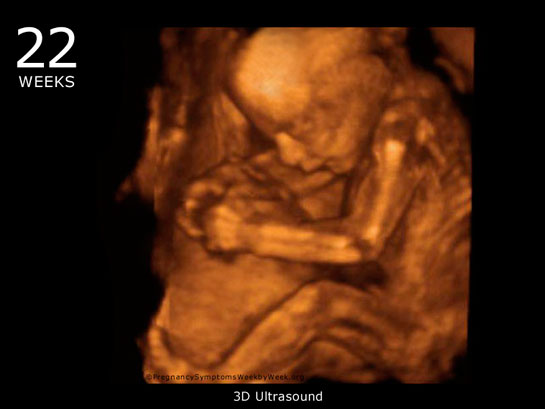

| 36 haftalık gebelik, bir hamilelik sürecinin önemli bir aşamasını temsil eder. Bu dönem, fetüsün gelişiminde kritik bir dönemdir ve anne adayının sağlığı bakımından da dikkate alınması gereken birçok faktör vardır. Bu makalede, 36 haftalık gebelik sürecinin özellikleri, anne adayı ve fetüs üzerindeki etkileri ile birlikte, bu dönemde dikkat edilmesi gereken konular ele alınacaktır. Fetüs Gelişimi 36 haftalık gebelikte fetüs, doğuma oldukça yakın bir dönemde bulunmaktadır. Bu aşamada fetüsün gelişimi ile ilgili bazı önemli noktalar şunlardır: